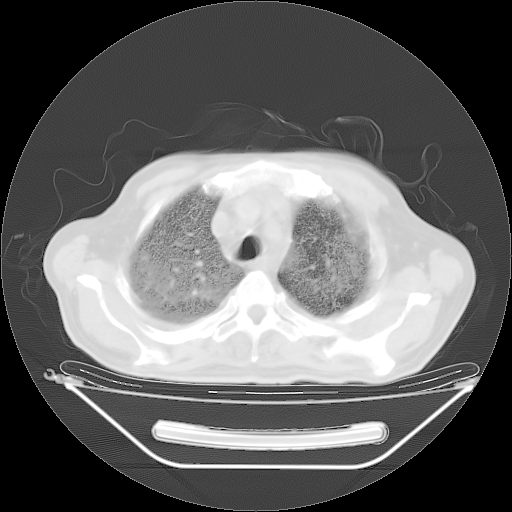

今天复查肺部CT,发现双肺广泛磨玻璃样改变。所以我把3月19日和5月9日相隔50天的肺部CT上传。请大家会诊。

2009年3月19日肺部CT片。

2009年3月19日肺部CT